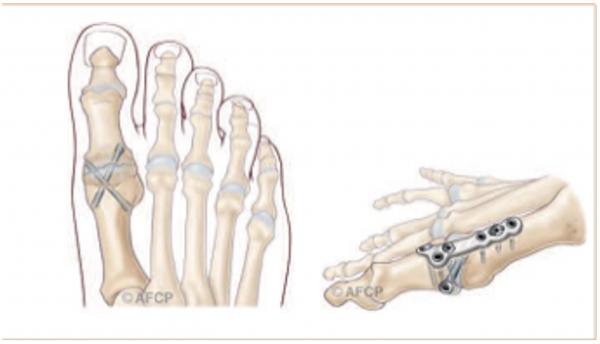

HALLUX VALGUS

Il s’agit d’une déformation qui crée une saillie osseuse sur la partie médiale de l’hallux, à l’origine de phénomènes douloureux et d’une gêne au chaussage. Il s’agit de la déformation la plus fréquente de l’hallux. Elle touche préférentiellement les femmes, parfois dès le plus jeune âge. On ne connaît pas réellement les causes de cette déformation mais l’origine congénitale semble la plus vraisemblable

Chirurgical :

Les techniques « conventionnelles (ciel ouvert) » permettant, sous contrôle de la vue de corriger la déformation.

Au contraire, les techniques « percutanées » utilisent plusieurs incisions millimétriques, permettant le passage d’instruments spécifiques qui sont guidés sous la peau par un contrôle radiographique.